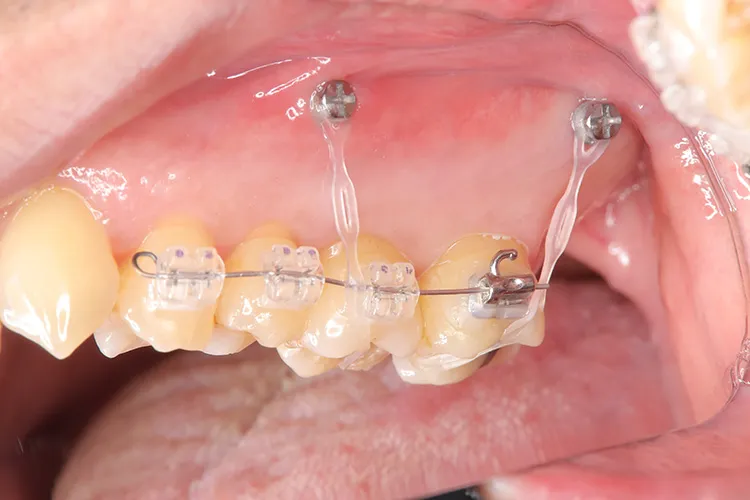

左下の大臼歯の欠損を長期間放置したために上の歯が下がってきてしまい、他の歯医者で被せを入れることができないと断られうちに来られました。下がってきてしまった上の奥歯を部分矯正で上に引っ張り上げ、下に被せ物を入れるスペースを作り、インプラントを入れて噛み合わせを回復しました。部分矯正開始から1年半で治療完了しました。

治療内容

左下67 欠損に対してインプラント治療を行った症例

部分床義歯を使用していたが、どうしても慣れない上にしっかり噛むことができないためインプラント治療を希望